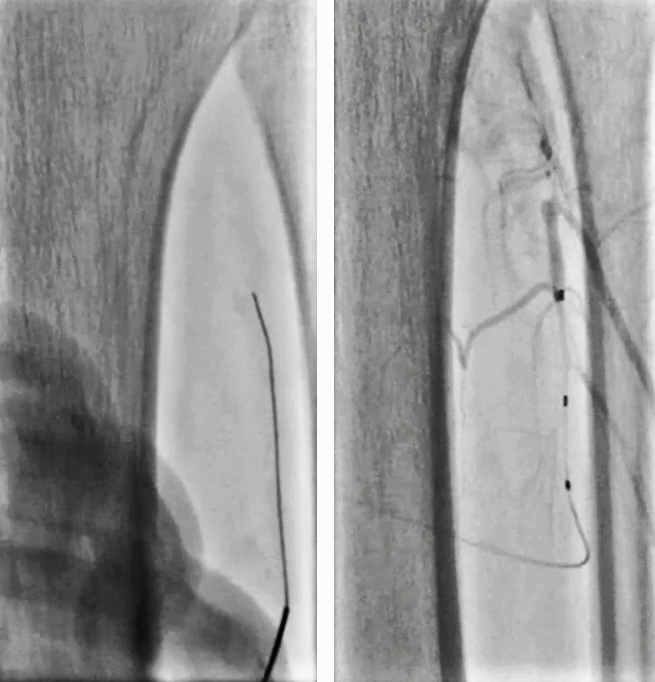

6. 将导管向远端推送跨过动脉瘤,造影见腘动脉P1P2交界处血管破裂,远端仍未显影;将导管推送至P2段,见造影剂外溢和远端夹层形成;

7. 造影发现腘动脉末端1cm可作为覆膜支架远端锚定区;自腘动脉末端至P1段置入5mm×100mm Viabahn;序贯置入7mm×100mm和7mm×50mm Viabahn,近端至内收肌管口水平,覆盖一个侧枝;6mm×200mm球囊后扩;

8.造影见动脉瘤消失、支架通畅、腘动脉远端狭窄和造影剂滞留;自近端将导丝置入腓动脉,3mm×60mm球囊扩张;造影见腓动脉形态良好,无造影剂滞留,见胫前动脉开口狭窄;